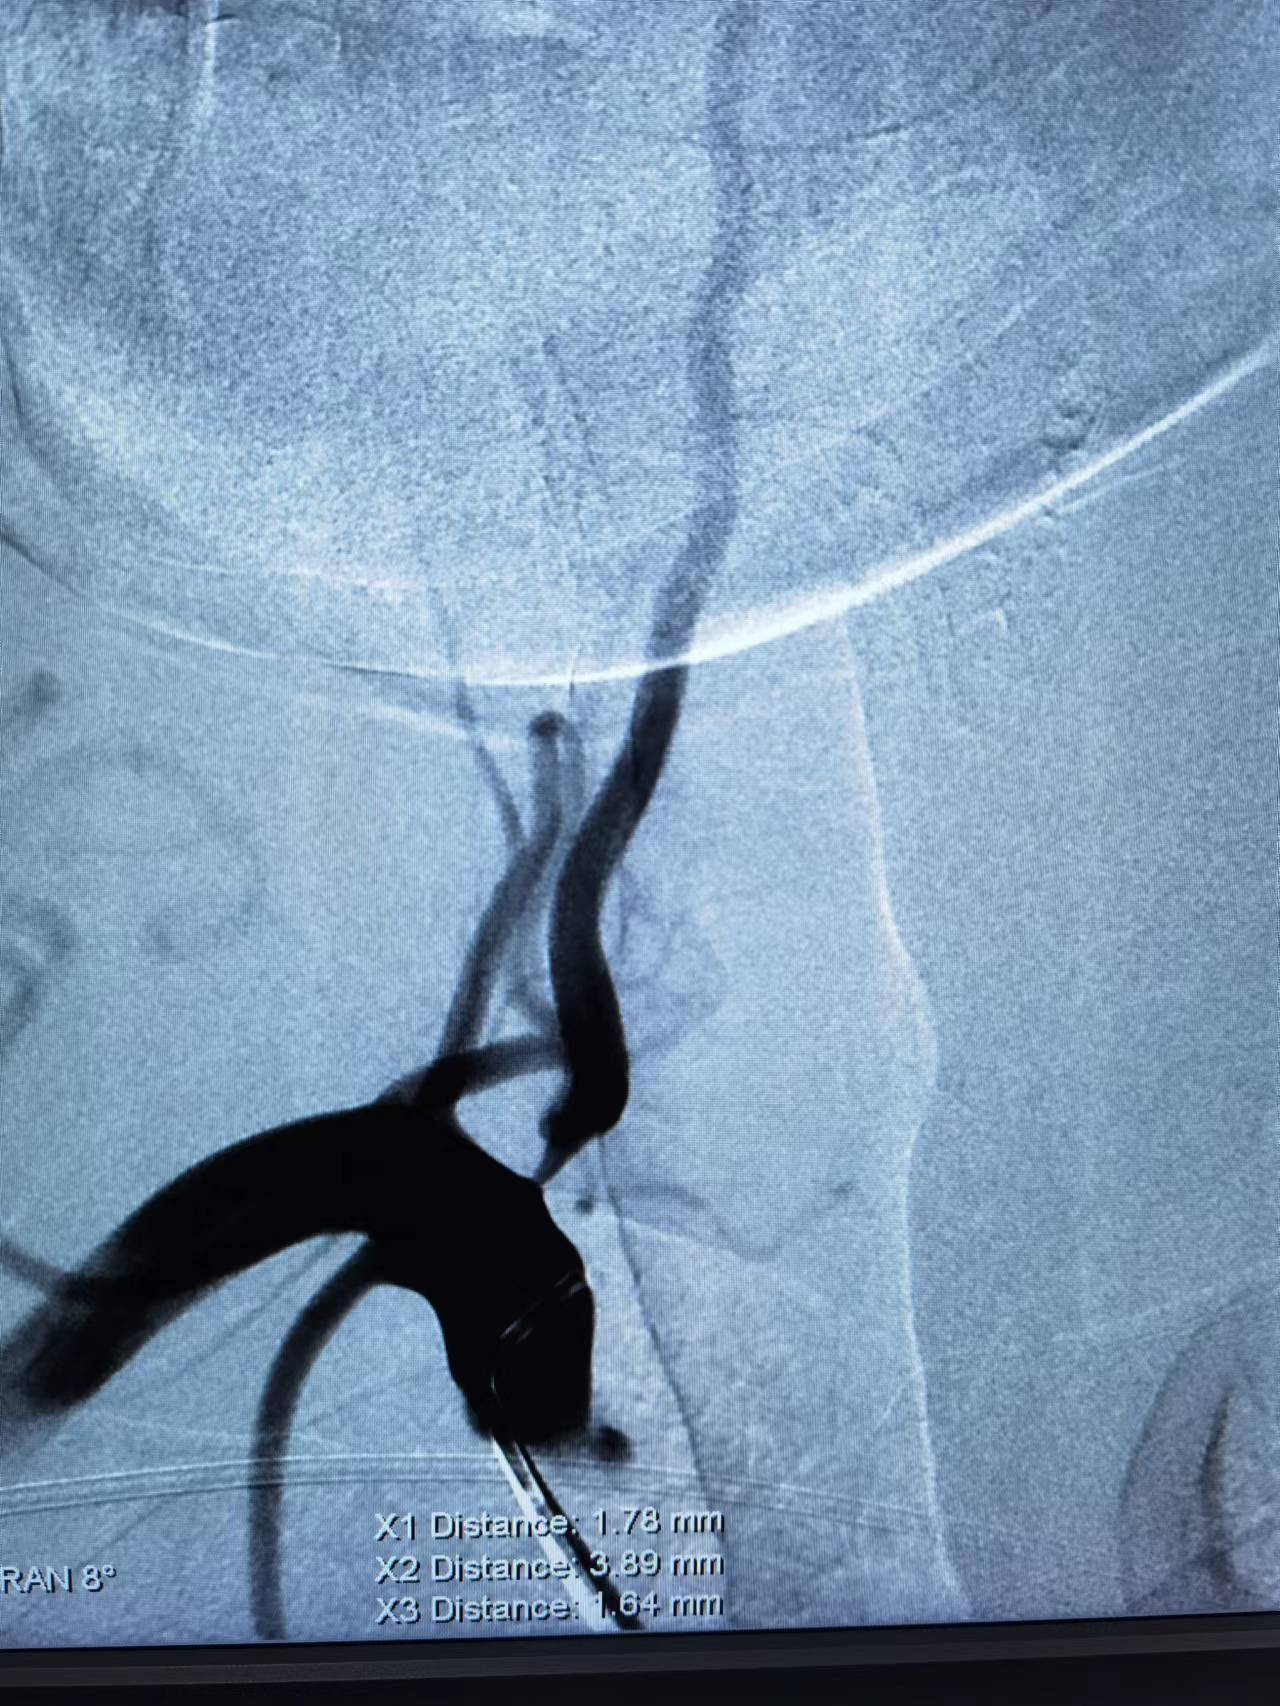

男性,76岁。因长期头晕、头昏,来到海南西部中心医院就诊。查超声提示双侧颈动脉重度狭窄,脑血管造影提示左侧颈内动脉百分之九十以上狭窄,右侧颈动脉百分之七十五以上狭窄。据悉,这种患者年脑梗发生率百分之二十以上,急需进行介入手术治疗。

术前DSA

神经内科介入团队在术前根据患者实际情况,制订了周密的术前预案,并与患者家属充分沟通,在得到家属支持并同意手术后,为患者实施了左侧颈动脉球囊扩张支架植入术。不到一个小时的时间,手术顺利完成,精确地将支架置于患者左侧颈动脉狭窄处,使其恢复正常血运,成功转危为安。

术后DSA